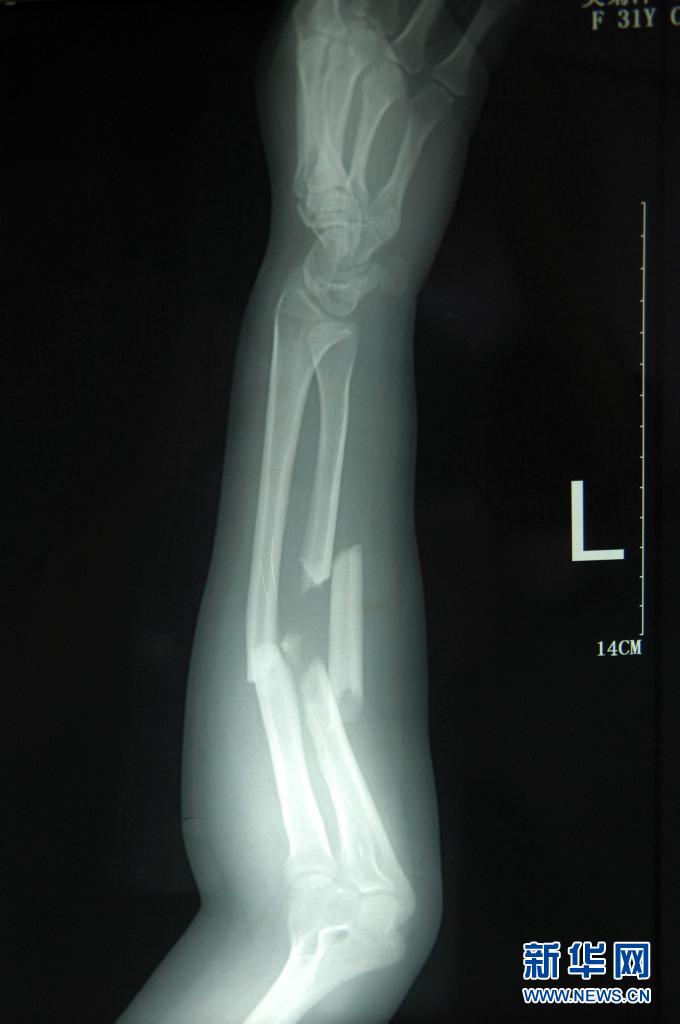

這是2011年7月3日拍攝的吳菊萍受傷左臂的X光片,醫生診斷為手臂左尺橈骨多段粉碎性骨折。新華社記者 黃宗治 攝